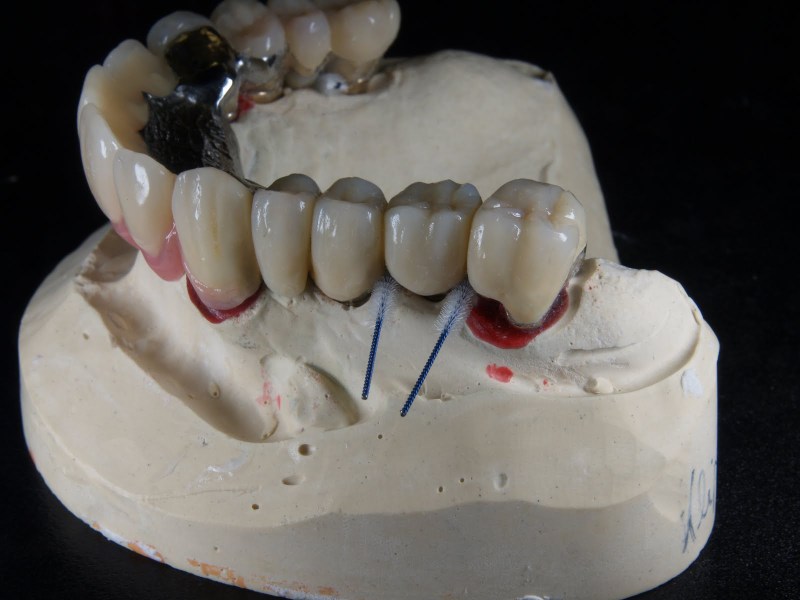

Nichtedelmetal NEM und Keramik